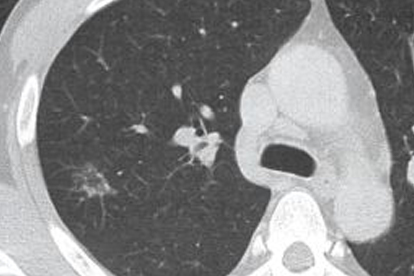

肺癌是一種常見的惡性腫瘤,其發(fā)病原因復(fù)雜,包括吸煙、空氣污染、職業(yè)暴露、遺傳因素等。早期診斷和規(guī)范治療對提高患者生存率至關(guān)重要。目前肺癌的治療方法包括手術(shù)、放療、化療、靶向治療和免疫治療等,需根據(jù)患者具體情況制定個體化方案。